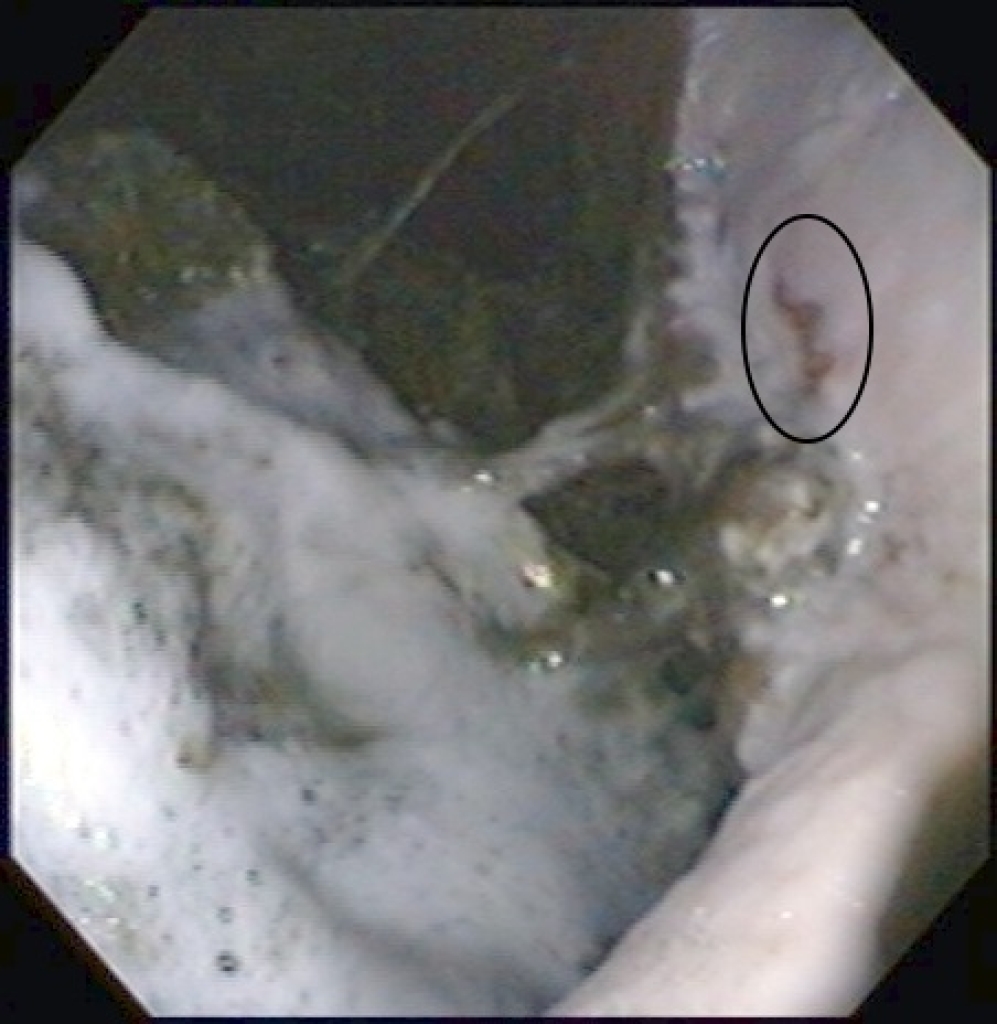

Maagulcera in het onderste gedeelte van de maag zien we wat minder vaak en zijn moeilijker om te behandelen. Ondanks wetenschappelijk onderzoek weten we  eigenlijk nog niet goed waarom  deze maagzweren ontstaan. Bij mensen komen vergelijkbare maagzweren voor, deze zijn veelal het gevolg van medicijn gebruik of een bacteriële infectie van de maagwand. Bij paarden is wel uit onderzoek gebleken dat bacteriën geen grote rol spelen in het ontstaan. Ook hebben veel paarden met dit type maagzweren geen medicijnen gebruikt die dit kunnen veroorzaken. Wat de achterliggende oorzaak is voor het ontstaan van deze zweren is dus nog niet goed bekend. Overigens is bij 30% van de maagzweren bij mensen de oorzaak ook niet bekend. Dit maakt dat deze maagzweren vaak lastiger te behandelen zijn en een langdurige behandeling vergen.

Links: Diepe maagzweren in het onderste gedeelte van de maag

Rechts: Maagzweren onderin de maag rondom de uitgang naar de dunne darm

Diepe maagzweren in het onderste gedeelte van de maag

Maagzweren onderin de maag rondom de uitgang naar de dunne darm